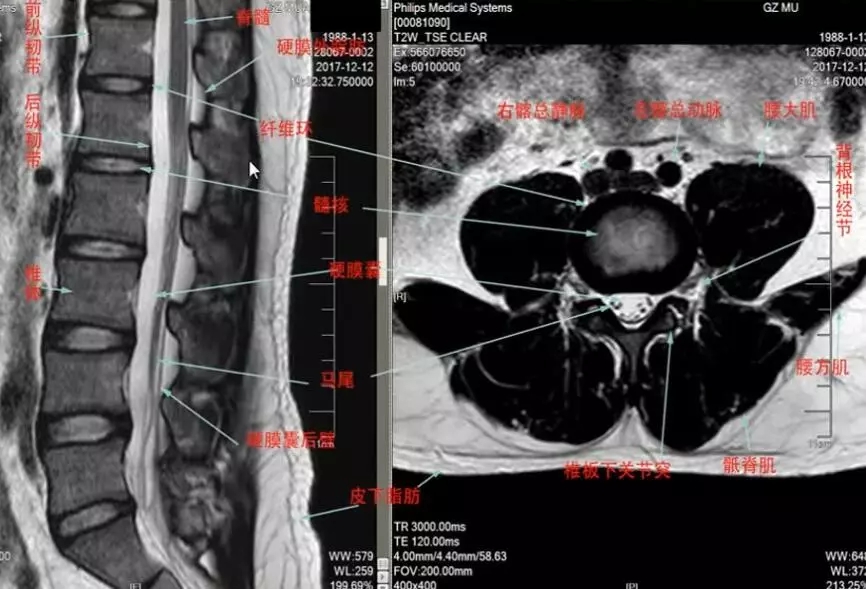

我们先来看一下脊柱脊髓mr的正常表现,可以看到前纵韧带,后纵韧带,椎体,脑脊液,脊髓,马尾神经,腰大肌,腰方肌等等

这是一个椎间盘突出引起的神经根型颈椎病,我们在矢状面可以看到这里有突出的椎间盘,在横断面也可以看到突出的椎间盘压迫了神经根,治疗原则主要是前路,摘取致压物,还有进行椎间融合,但目前也有经椎间孔镜通后路进行致压物的摘取。根性颈椎病的预后,如果是单纯的椎间不稳,椎间盘突出或者脱出的,预后比较好,如果是由于钩椎关节增生导致根袖黏连,这样的病例症状会发生延续,预后较差。如果是广泛性的骨质增生造成的压迫,发生了变性,预后则更差